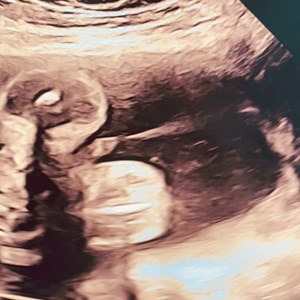

28. juni 2024

Fredagens sidste lille baby på briksen 🤓🩵 Han er ca 1200 gram i uge 28+1, og derfor meg...